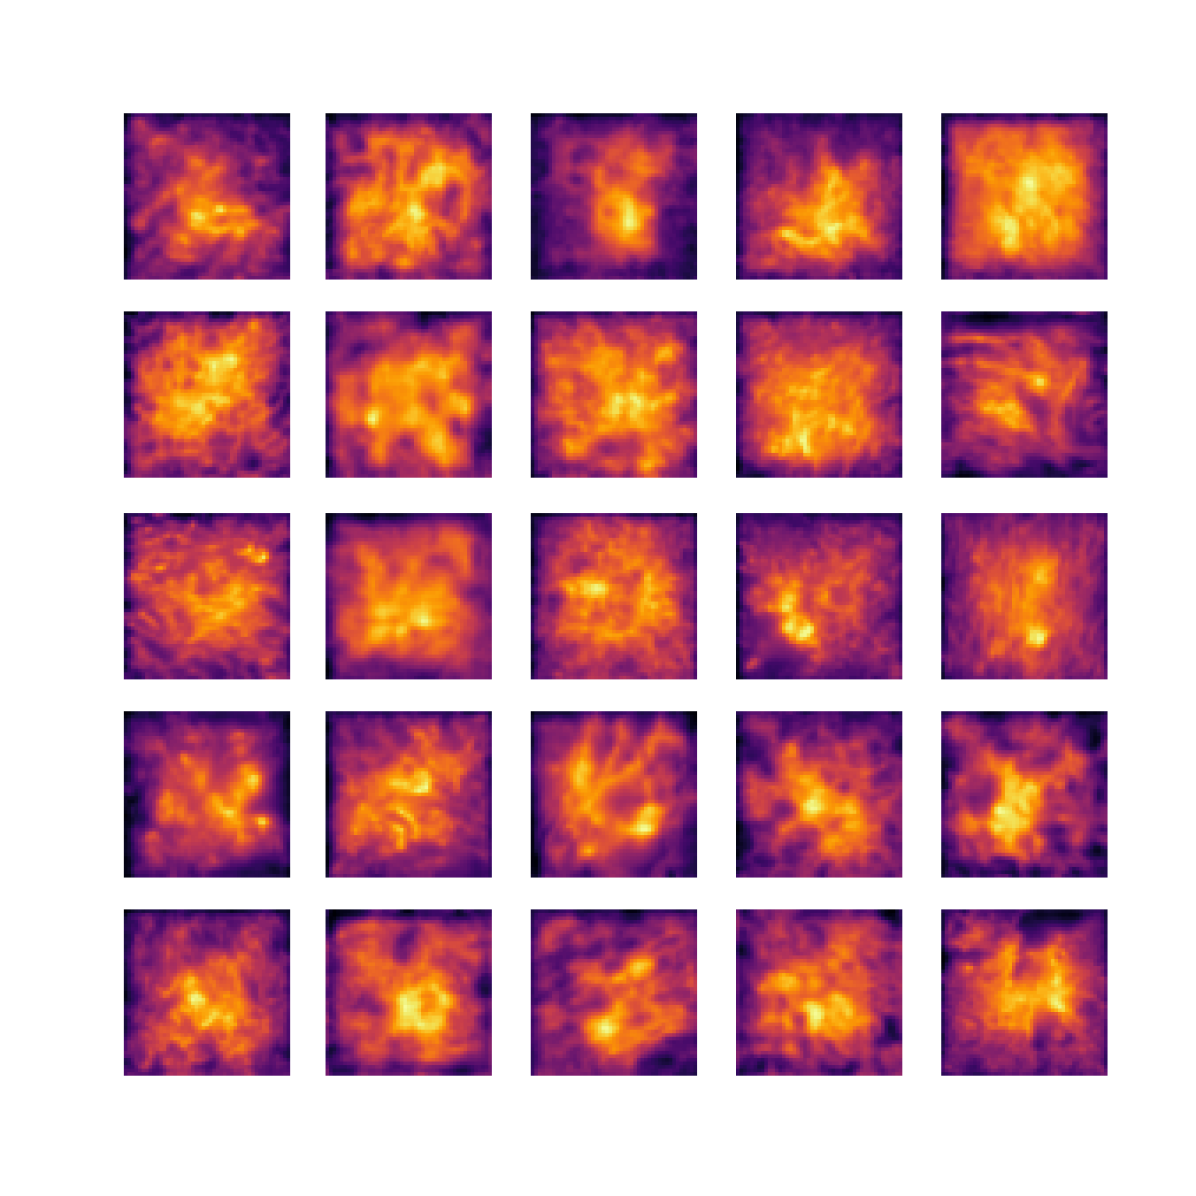

We also analyse the activation maps for each model using GradCAM as described in section S3. This offers more insight into the areas of the image which are contributing most heavily to the models’ representations. In Figure 4(b) we present some representative examples, however, a larger selection which was chosen at random is presented in Figures S10 to S25. The larger selection makes it easier to see the emergent patterns, including that privileged Siamese models tend to mainly identify features which are strongly present in both inputs, while unprivileged Siamese models tend to learn more diffuse features that are not specific to one cell phenotype or image region. TriDeNT ♆ incorporates both sets of features, learning both features specific to the privileged data and more the general features associated with unprivileged Siamese networks.

We can see in Figure 4(b) panel A that for ERG, the privileged Siamese model focuses almost exclusively on any nuclei which could be endothelial cells. As there are very few endothelial cells in the dataset, it could be an effective strategy to identify anything that could potentially be an endothelial cell to minimise the difference between the representations of the H&E model and the IF mask model. In the corresponding unprivileged Siamese image, we see that the model identifies some of these nuclei, albeit less strongly, but also focuses heavily on the other tissue and even the background, while strongly fixating on two spots of debris in the center of the image. This model has less ‘incentive’ to learn the weak features related to endothelial cells as these occur rarely and are not easy to detect, while more generic strong features such as the presence of connective tissue and the prevalence of background are more common and predictable from augmented images. We see that TriDeNT ♆ combines these two feature sets, strongly identifying nuclei while also identifying the connective tissue.

In panel C we see a similar pattern, with the privileged Siamese model fixating solely on the nuclei, while the TriDeNT ♆ model takes a more balanced approach. The unprivileged Siamese model appears to focus on a single cluster of nuclei while neglecting others, and similarly identifies an area of fibroblasts with its distinctive pattern but does not others.

In contrast to panels A and C which represent models with poor privileged Siamese results, panels B and D represent models whose privileged Siamese results were comparable to both TriDeNT ♆ and even the supervised baseline. It is therefore interesting to note that there are far more similarities between the privileged Siamese and TriDeNT ♆ models in both cases. Particularly in panel B, TriDeNT ♆ and the privileged Siamese model return virtually identical heatmaps, with both strongly identifying epithelial nuclei and neglecting the same areas of connective tissue. The unprivileged model in this case appears to focus solely on the centre of the image, giving a significantly different heatmap to the other panels.

Panel D again shows the previous pattern, with the privileged Siamese model identifying the features strongly present in the privileged data – fibroblasts – while neglecting the nuclei present. TriDeNT ♆ also strongly identifies the connective tissue, but, unlike the privileged Siamese model, does not completely neglect the nuclei. The unprivileged Siamese model primarily identifies background, and does not appear to identify the nuclei in this example.